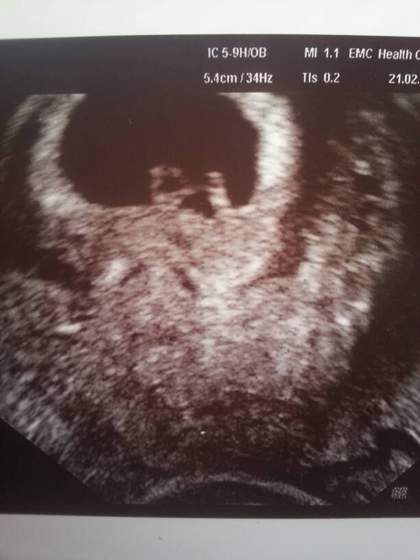

(tu sie pocieszam) , w poprzedniej ciazy robilismy zdjeica praktycznie co tydzien (paru nam brakowalo) i teraz zamierzamy robic w te same tygodnie. Super prezentacja nam potem wyszla